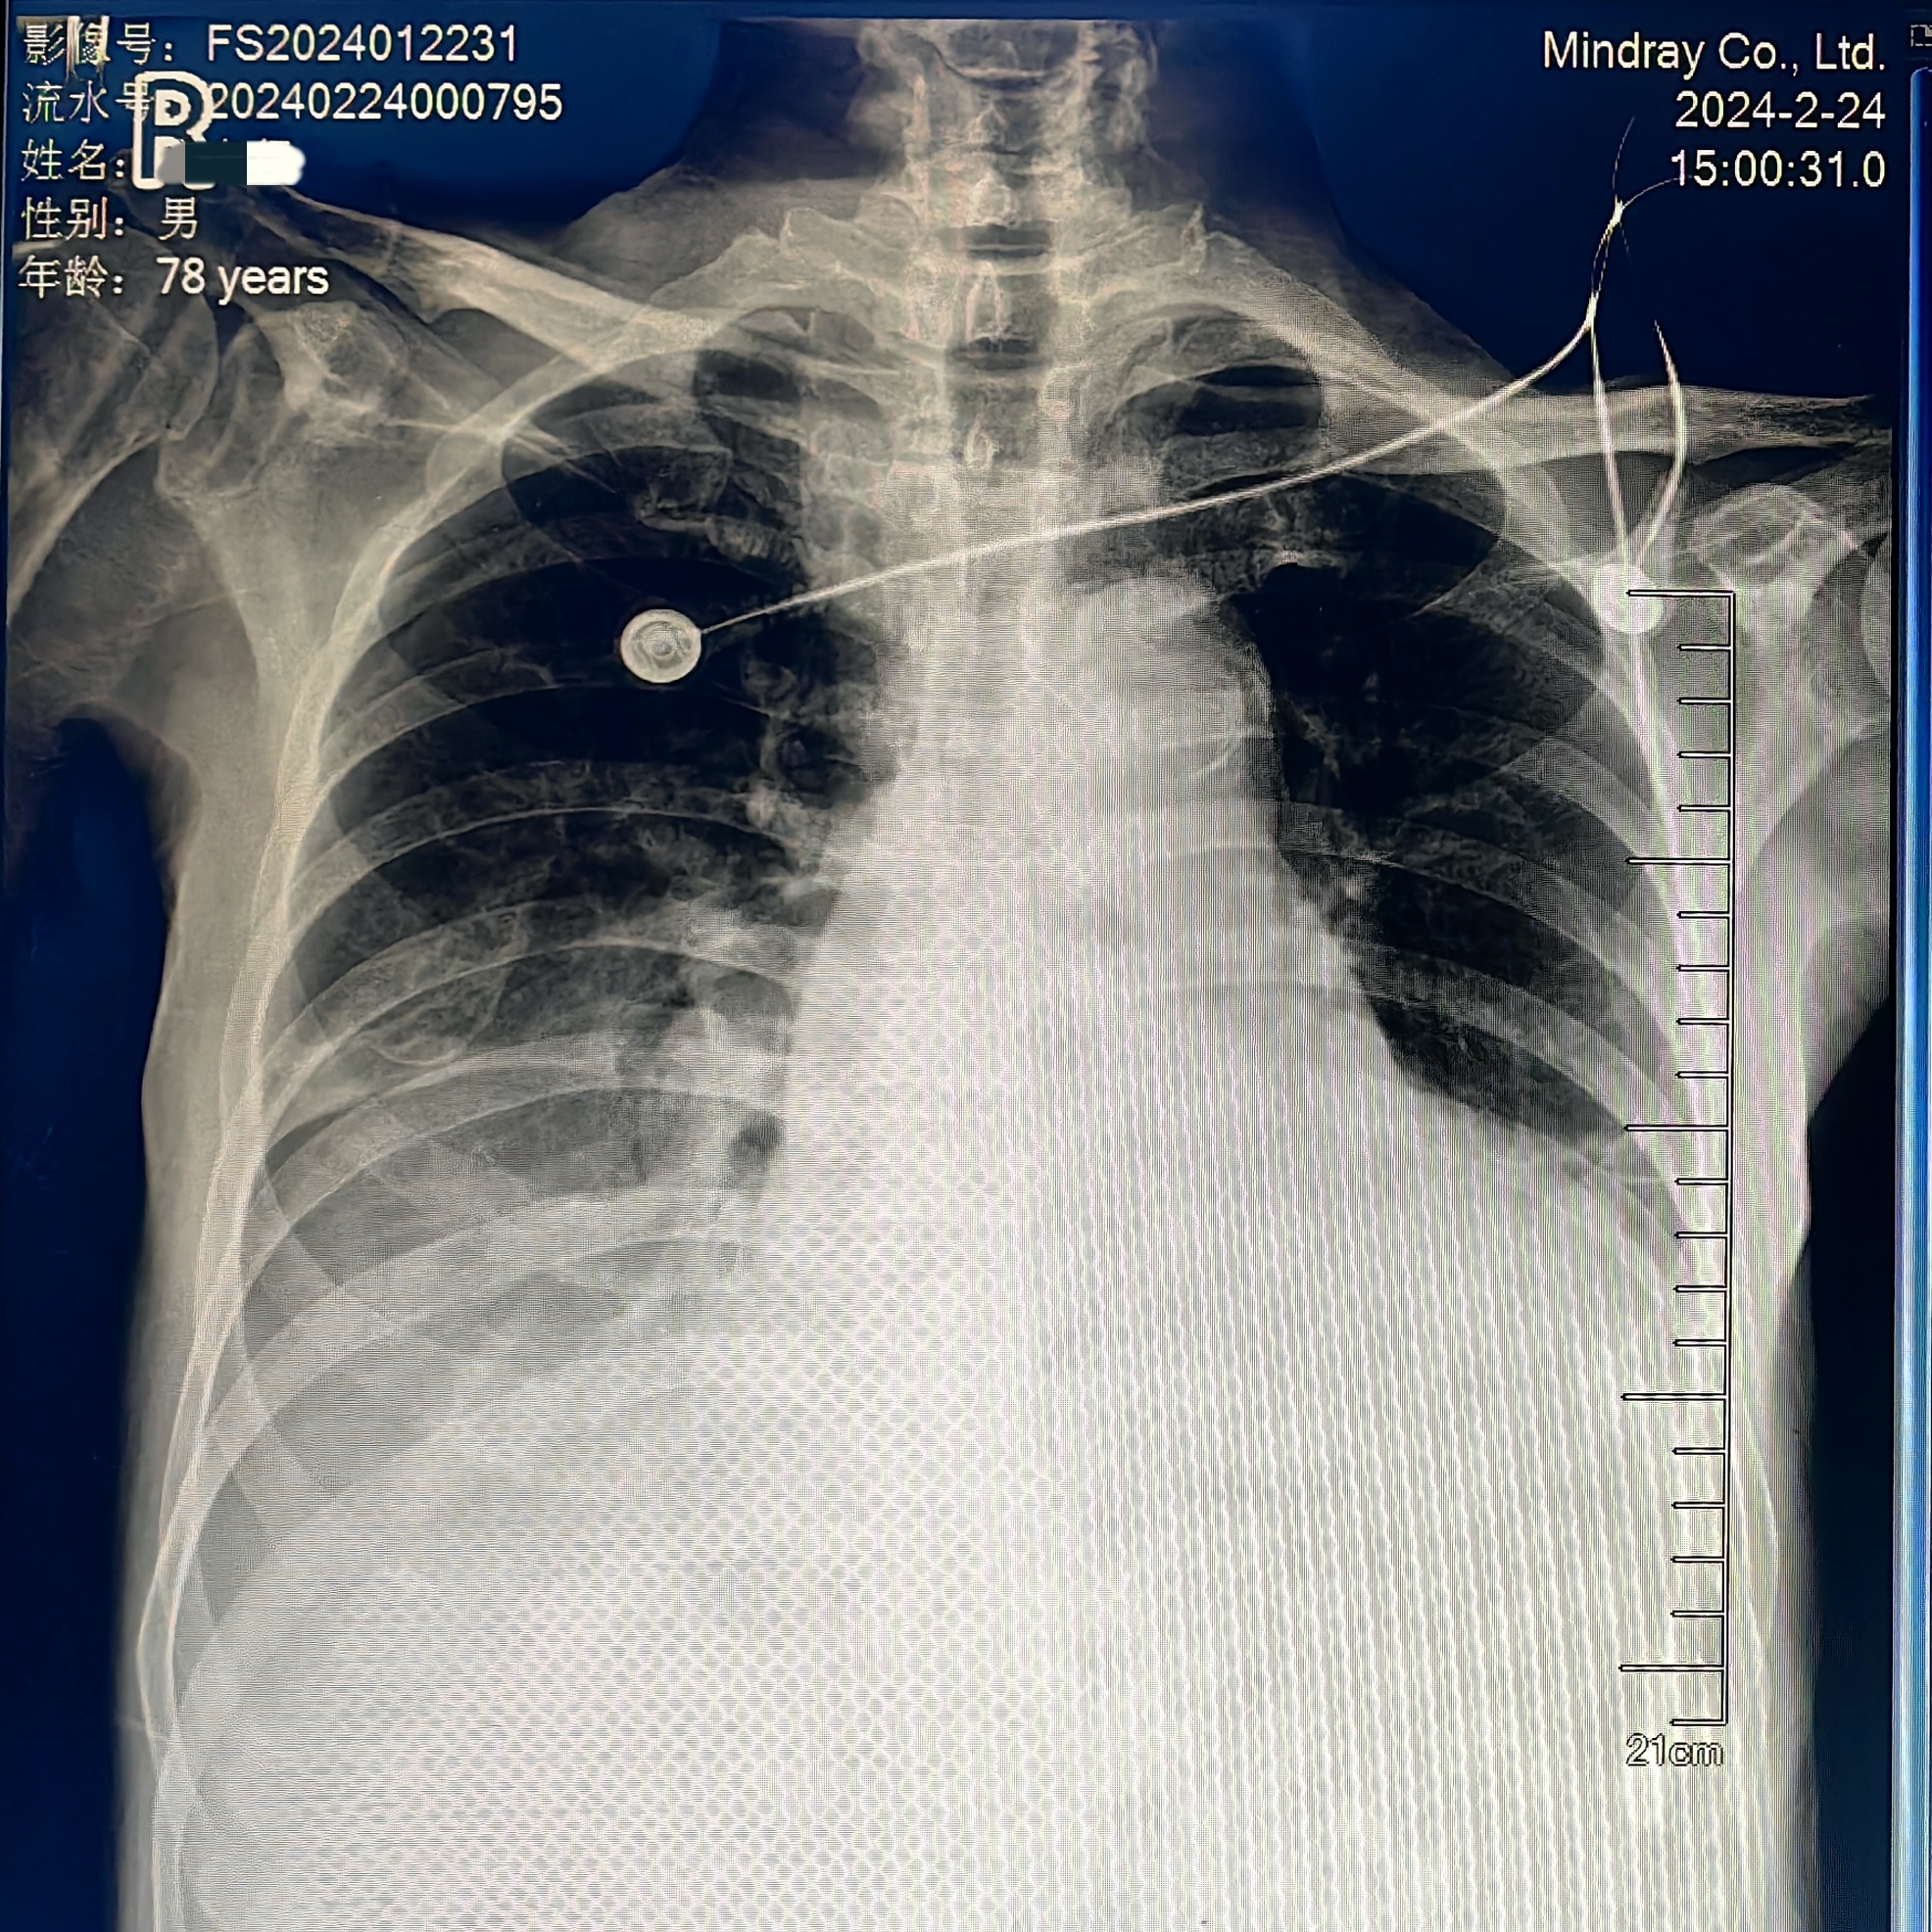

老唐的术后康复之路也十分坎坷,先后经历了一系列惊心动魄的抢救和治疗(II 型呼吸衰竭需要再次气管插管、肾功能损害加重需要连夜紧急床旁血液透析、III°房室传导阻滞需要安装心脏永久起搏器、贫血、血小板减少等),抢救过程步步惊心。